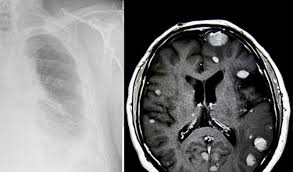

In the largest study to date on the link between firefighting foam and kidney cancer risk, researchers found evidence to suggest that people with higher concentrations of pfas in their blood serum were more than twice as likely to develop kidney cancer compared to those with lower concentrations of the chemicals. Here, we report the case of a kidney transplant patient for 2 years with malignant pleural effusion that was subsequently diagnosed as malignant pleural mesothelioma. Malignant mesothelioma is a rare cancer with no cure. The less common, peritoneal mesothelioma, is found in the lining of the abdomen, and is generally harder to treat. Neuroendocrine tumor of the lung; Relative risk for each cancer by Research applications in the areas of breast, prostate, lung (excluding mesothelioma), kidney, melanoma, pancreatic, rare cancer, or ovarian cancer will not be accepted. It is not a lung cancer but it is a cancer of the covering of the lung that is known as a pleura. Melanoma, sarcoma, kidney cancer, merkel cell carcinoma. mesothelioma meme,mesothelioma causes,mesothelioma definition,mesothelioma symptoms,mesothelioma prognosis,mesothelioma treatment,mesothelioma what is it,mesothelioma lawsuit,mesothelioma survival rates,mesothelioma law firm,mesothelioma,mesothelioma commercial,mesothelioma cancer,mesothelioma ad,mesothelioma ad script,mesothelioma awareness,mesothelioma applied research foundation. What kind of cancer is a pleural mesothelioma? See more ideas about mesothelioma, treatment, cancer. Navy ships built before 1980.

It is intended as a resource to inform and assist clinicians who care for cancer patients. Research applications in the areas of breast, prostate, lung (excluding mesothelioma), kidney, melanoma, pancreatic, rare cancer, or ovarian cancer will not be accepted. Malignant pleural mesothelioma is a malignant or cancerous tumor of the pleura, the mesothelium that surrounds the lungs. Allogeneic tumor cell vaccine biological: Peritoneal mesothelioma begins with tumor development in the peritoneum, the thin.